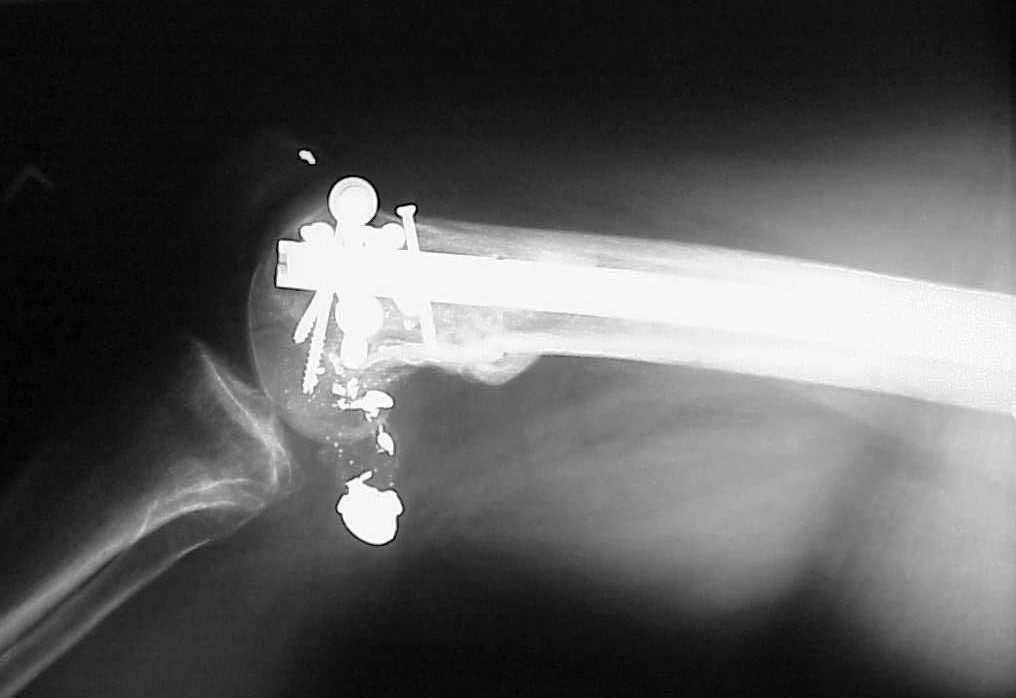

place one anterior to where IMN will go if anterior cortex if insufficient and AP screws on either side of the IMN out of the trochlea to provide some additional varus/valgus stability. I worry about the leg going into valgus w/the lack of lateral cortex.

See attached case that was done several years ago before LISS. He had comminuted trochlea and anterior blocking screws were used to prevent anterior IMN cut-out.